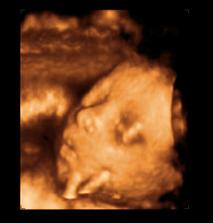

26 tt../1.4.2009/ naša paulínka je stráášne zlatá, boli sme si pozrieť na 4D utz. ..tvárila sa veľmi dôležito, až nafúkano...hehe..vôbec sa nechcela usmievať... nakoniec sa nám aj zasmiala...v brušku veľmi vyvádza, maminke dosť vytláča všetky časti telíčka, čo je niekedy aj dosť bolestivé...ale vydržíme, drobečkovi je tam určite tiež pritesno..a ešte aj stále viac a viac bude... strááášne sa na ňu tešíme🙂))